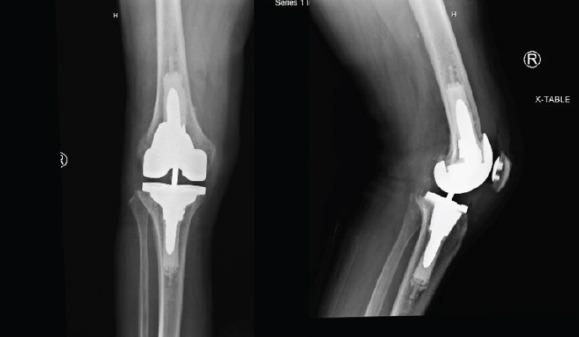

We present a case describing a novel technique in which the Mako robot (Stryker, Ft. Lauderdale, FL) was utilized for revision of a failed primary TKA secondary to aseptic loosening. The patient is a 68-year-old Caucasian male who underwent right revision TKA with robotic assistance. Stryker Triathlon TS implants were utilized with the use of both femoral and tibial cones and medial and lateral posterior femoral augments. He had satisfactory component alignment based on postoperative radiographs, and excellent clinical outcomes 6 months postoperatively.

我们介绍了一个病例,描述了一种新技术,即使用Mako机器人(史赛克公司,佛罗里达州劳德代尔堡)对因无菌性松动导致初次TKA失败的患者进行翻修。患者是一名68岁的白人男性,在机器人辅助下接受了右膝翻修TKA。使用了史赛克Triathlon TS植入物,包括股骨和胫骨锥体以及股骨内外侧后髁增大装置。根据术后X光片,假体排列满意,术后6个月临床效果良好。